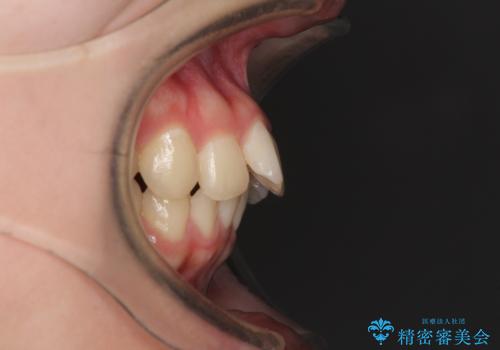

- 前歯2本が飛び出してることを気にして来院された患者様です。

全体的に黄ばんだ歯の色も気になるとのことで、マウスピース矯正により飛び出した前歯を治しつつ、ホームホワイトニングを併用して黄ばみを解消していくこととしました。

歯と歯の間を削ることで、飛び出した前歯が引っ込み、スッキリとした口元となりました。